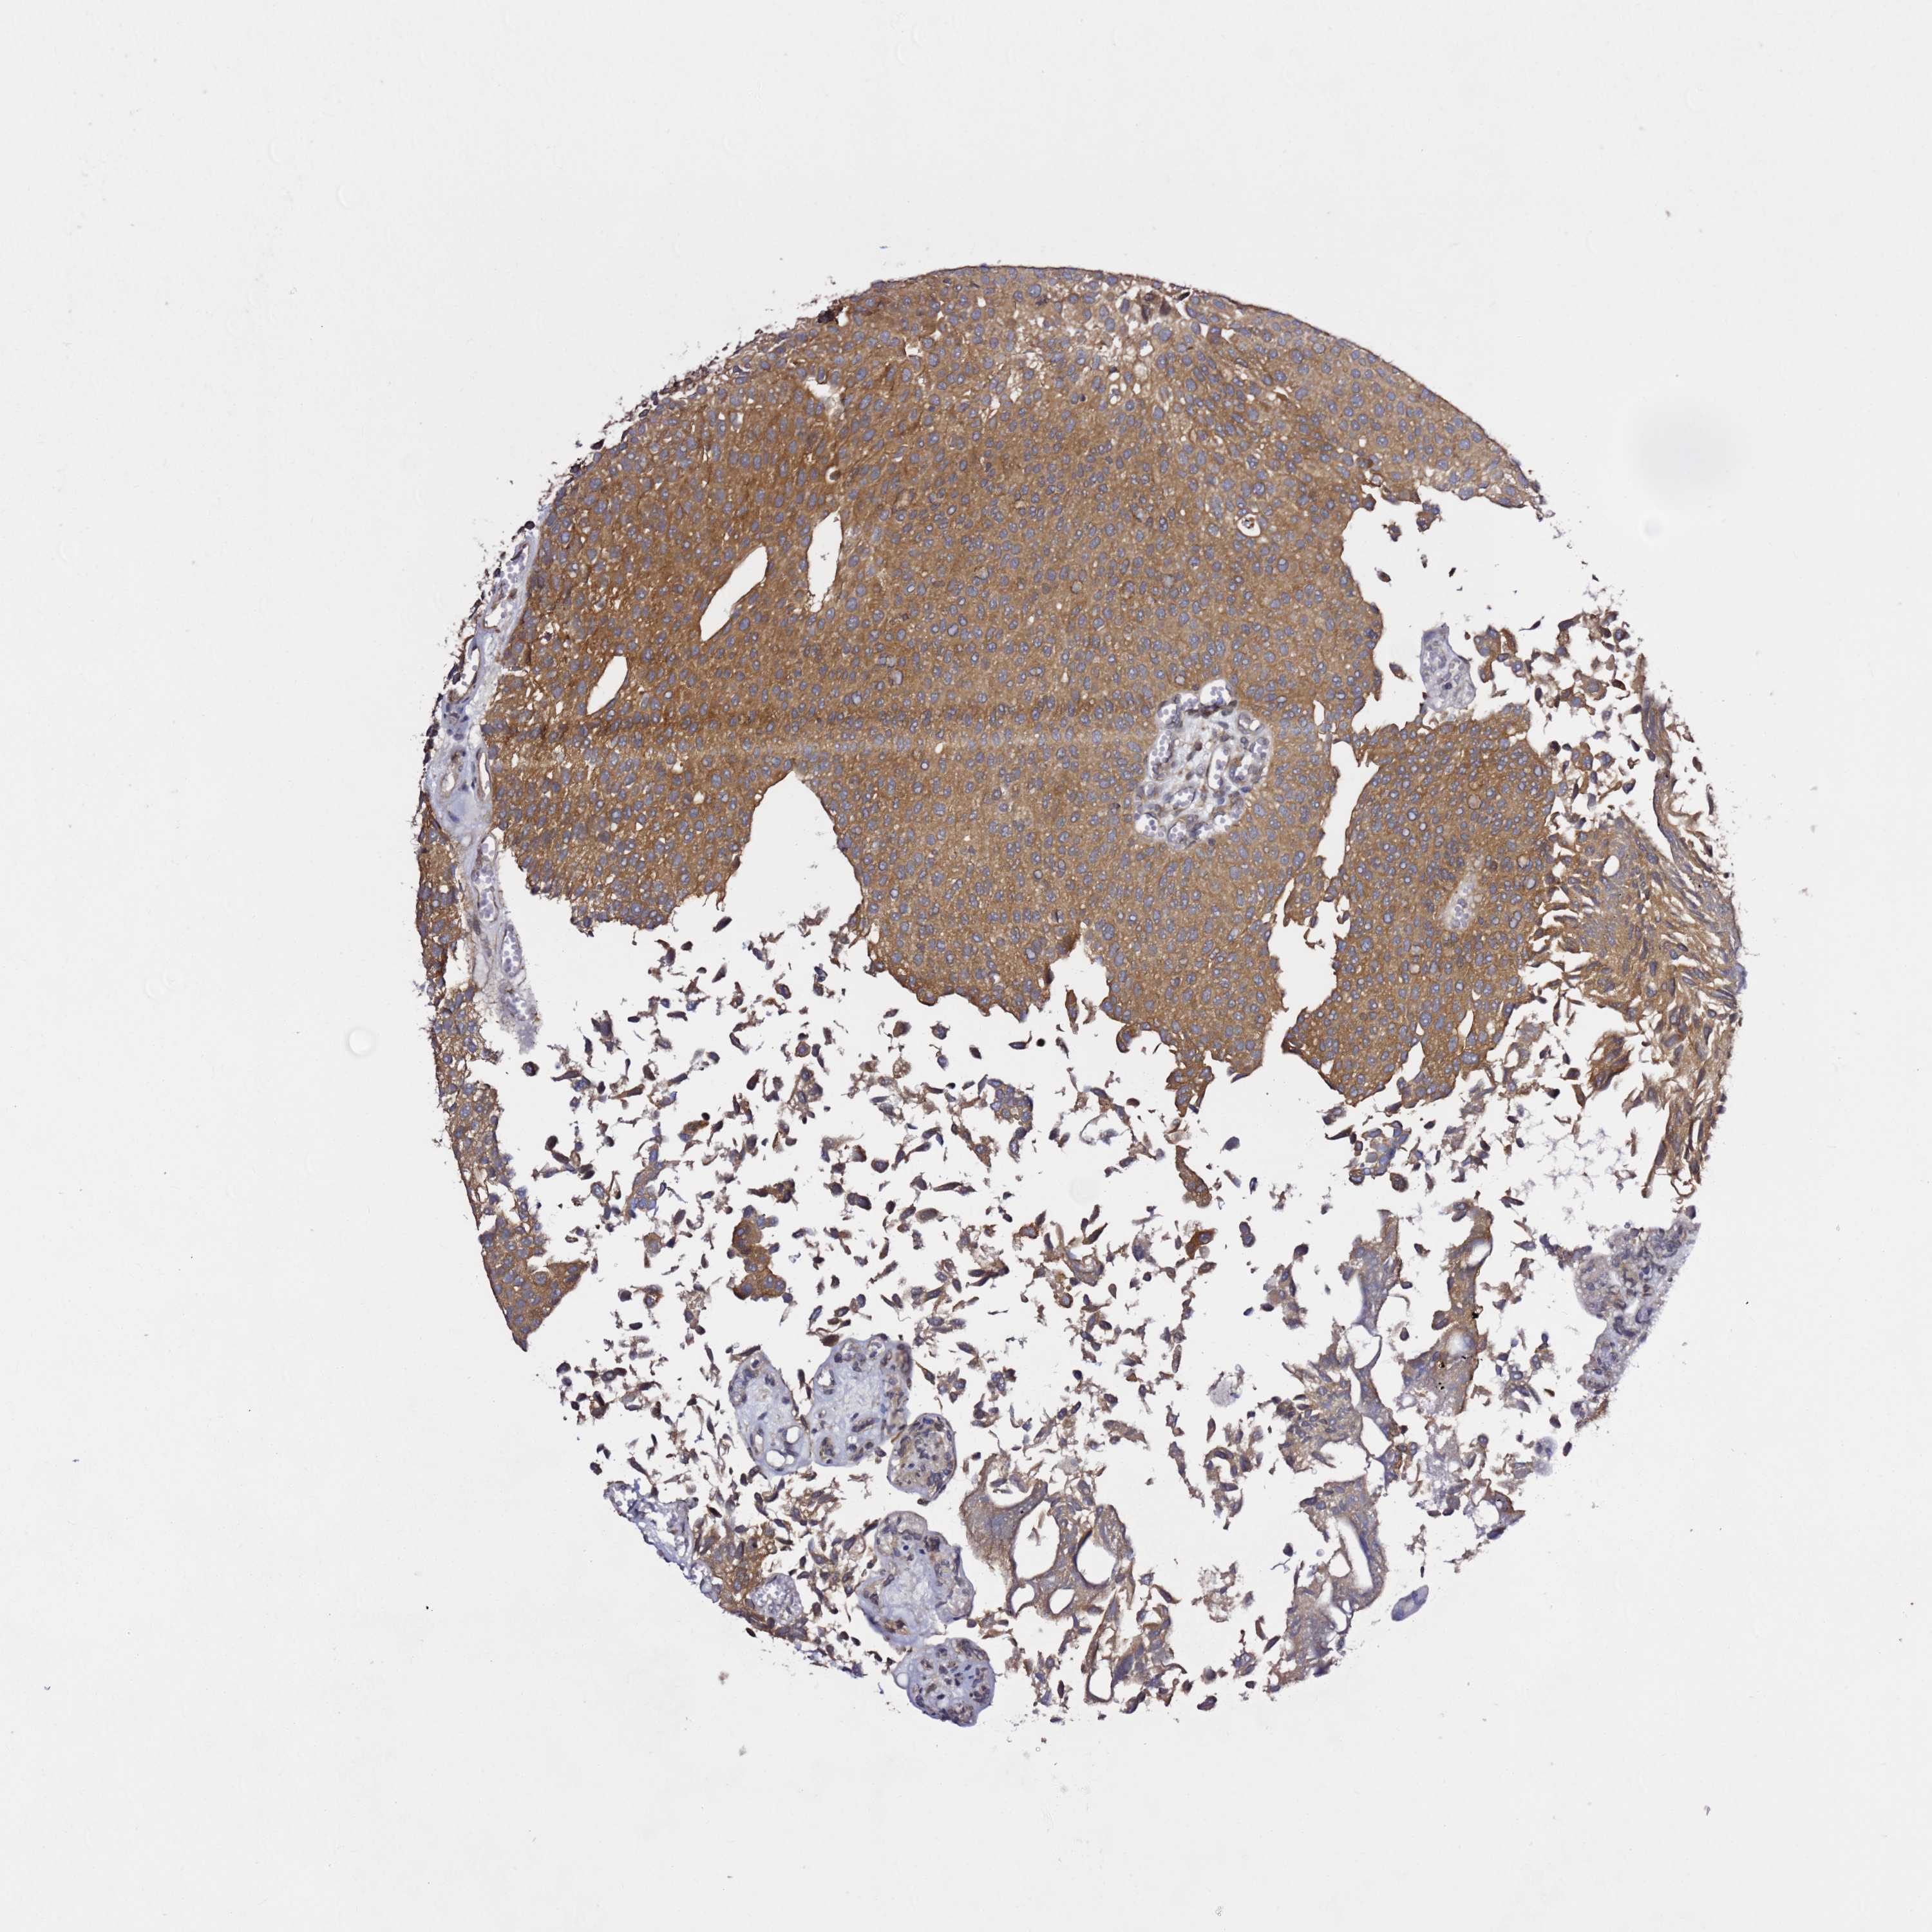

UROTHELIAL CANCER - Protein expressioni

A mouse-over function shows sample information and annotation data. Click on an image to view it in a full screen mode. Samples can be filtered based on level of antibody staining by selecting one or several of the following categories: high, medium, low and not detected. The assay and annotation is described here.

Antibody stainingi

Antibody staining in the annotated cell types in the current human tissue is reported as not detected, low, medium, or high, based on conventional immunohistochemistry profiling in selected tissues. This score is based on the combination of the staining intensity and fraction of stained cells.

Each image is clickable and will lead to virtual microscopy that enables deeper exploration of all samples and also displays staining intensity scores, fraction scores and subcellular localization as well as patient and tissue information for each sample.

Antibody HPA044342

Staining

High

Medium

Low

Not detected

Intensity

Strong

Moderate

Weak

Negative

Quantity

>75%

75%-25%

<25%

None

Location

Nuclear

Cytoplasmic/membranous

Cytoplasmic/membranous,nuclear

Urothelial carcinoma, Low grade

Urothelial carcinoma, High grade

Urothelial carcinoma, NOS